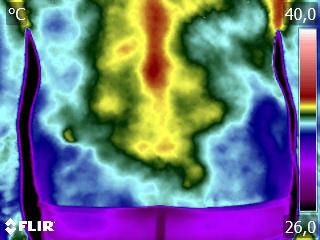

Como no caso dos termogramas abaixo de um paciente do sexo masculino, 44 anos, sem comorbidades e que apresentou dor em cervical. Foi realizado uma Análise Termofuncional e detectado alterações térmicas condizentes com o relato de dor.

Com estes achados foi possível determinar a cadeia postural que acometia o paciente, determinando o seu tratamento.

Somente com o conhecimento integral do Método de Termografia Infravermelha é possível detectar alterações e associá-las a uma disfunção.